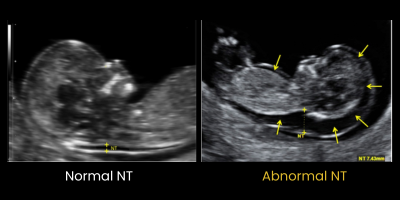

The Nuchal Translucency (NT) Scan is a critical component of first-trimester screening conducted between 11 and 14 weeks of pregnancy. The NT scan is a specialized ultrasound Scan that is done by a trained fetal medicine specialist, to assess the baby’s risk of chromosomal abnormalities, such as Down syndrome (Trisomy 21), Edwards syndrome (Trisomy 18), or Patau syndrome (Trisomy 13).  By measuring the fluid thickness at the back of the baby's neck, this scan, combined with blood tests, provides a detailed risk profile for genetic conditions.  Normal NT Scan Vs Abnormal NT measurement

NT refers to the fluid-filled space at the back of the baby’s neck, measured via ultrasound between 11 and 14 weeks of pregnancy.

Increased NT thickness is associated with a higher risk of chromosomal abnormalities, including Down syndrome. It may also indicate heart defects or other genetic conditions.